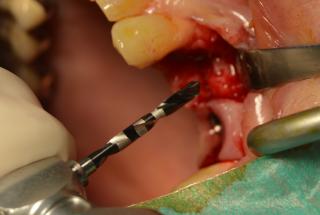

Clinical cases

MPI closely monitors clinical cases in the market to ensure their correct functioning and successful outcome.